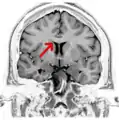

Вінцева Т2 МРТ головного мозку на рівні хвостатого ядра з підкресленням мозолистого тіла